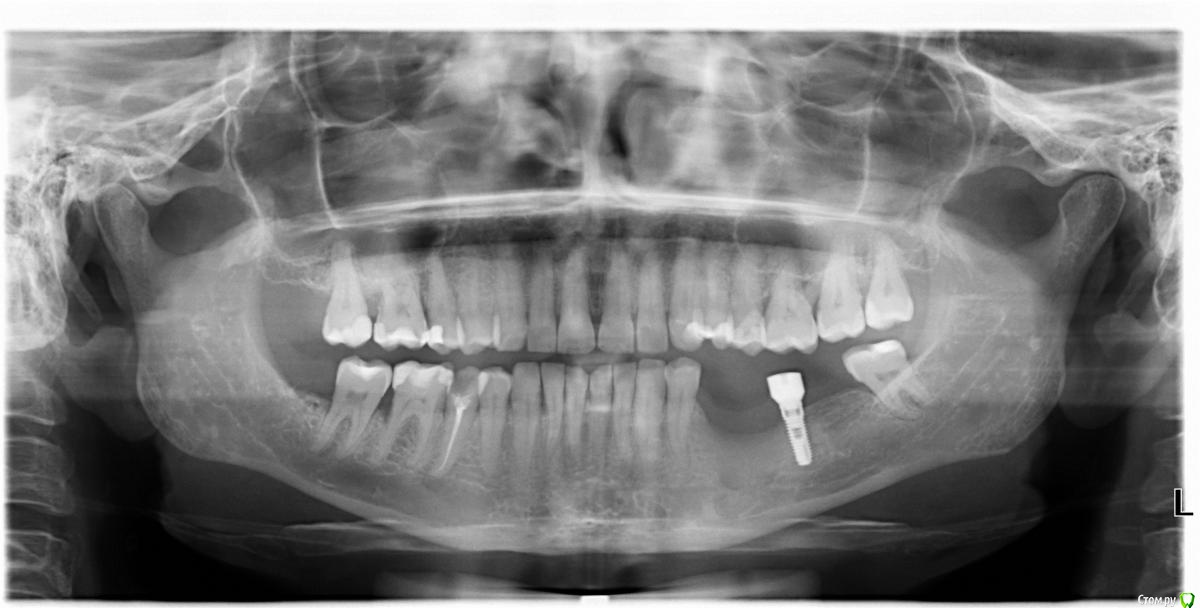

Eddie Опубликовано 30 октября, 2018 Поделиться Опубликовано 30 октября, 2018 Коллеги, подскажите, что за имплантат, стоит 10 лет непротезированным Ссылка на комментарий

Nazim_NV86 Опубликовано 30 октября, 2018 Поделиться Опубликовано 30 октября, 2018 (изменено) На impro похож...Что за формирователь ? Изменено 30 октября, 2018 пользователем Nazim_NV86 Ссылка на комментарий

КДБ Опубликовано 31 октября, 2018 Поделиться Опубликовано 31 октября, 2018 судя по всему был еще 1 имплантат,в результате его потери такой дефект...Учитывая,что на сег день условия стали не столь хороши,да и идентифицировать оставшийся сложно(да и нужно ли)-удаление его более правильное решение.Хотя нет-можно проститься с пациентом еще на 10 лет Ссылка на комментарий

Eddie Опубликовано 31 октября, 2018 Автор Поделиться Опубликовано 31 октября, 2018 В данном случае рассматриваю только удаление, вопрос в том, выкрутить ли имплантоводом, если узнаю систему или заказывать инструмент для удаления? Ссылка на комментарий

red_butler Опубликовано 31 октября, 2018 Поделиться Опубликовано 31 октября, 2018 на MIS позапрошлого поколения похож, BIOCON Ссылка на комментарий